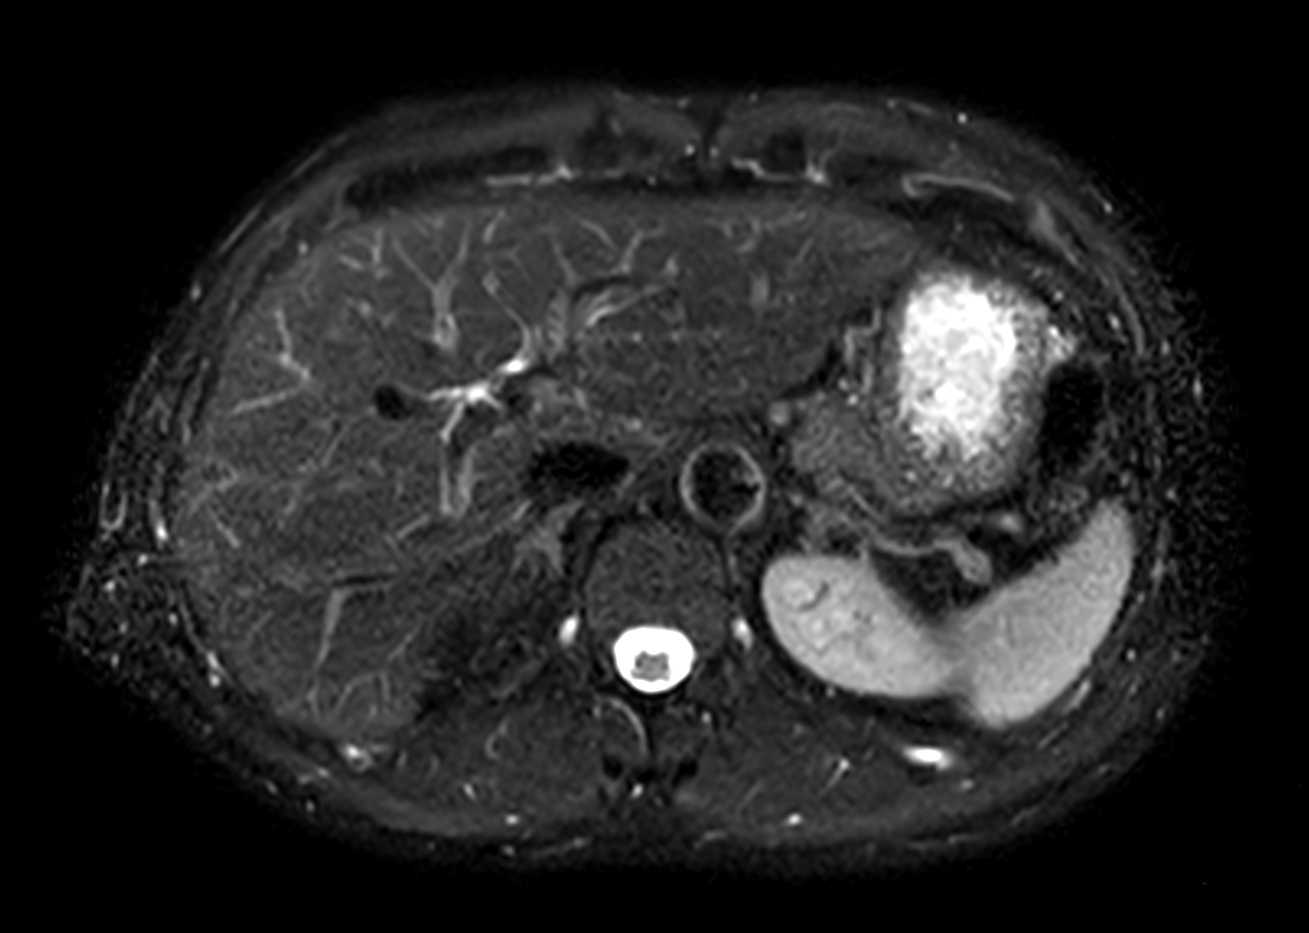

Liver on BlueSeal magnet

Spital Uster, Switzerland